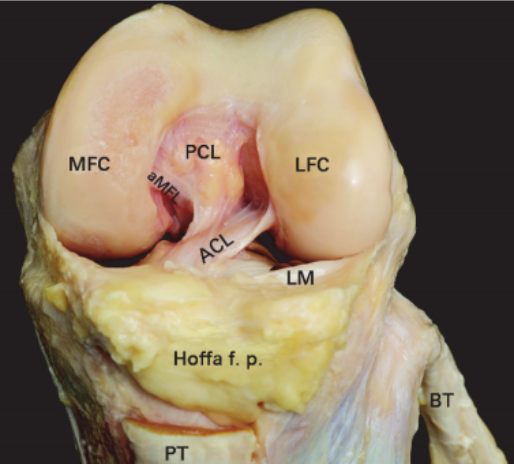

ACL 解剖

前交叉韧带起自股骨外侧髁的内侧面,斜向前下方,止于胫骨髁间隆起的前部。ACL 分为前内束(AM)和后外束(PL)。当屈膝 30° ~ 40° 时,前交叉韧带的张力最小。